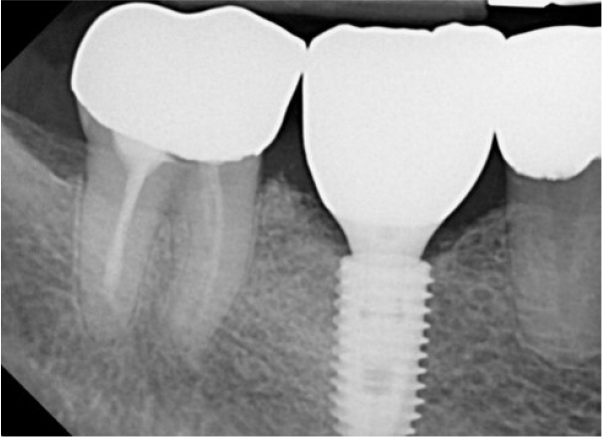

A 55-year-old man visited the clinic for implant discomfort and bleeding. The implant in the lower right 1st molar was placed three years ago at a private practice and was found to exhibit symptoms of buccal mucosal swelling and mesio-buccal deep probing pocket (Table 1). A sclerotic line on the fixture middle level was observed on panoramic and periapical radiographs (Figs. 1 and 2). There was no mobility or pus discharge but a throbbing pain during function. The probing depth was 10 mm; therefore, he was diagnosed with peri-implantitis, and we recommended implant removal. Patient hoped preservation, so regenerative therapy were preceded.

Definite implant failure is defined as pain or mobility during use or radiological bone loss of >50% of the implant length. In this case, radiologic radiolucency revealed necrosis occurring in the lower part of the implant, such as apical lesions, It appeared as an implant apical lesion caused by remnant endodontic or apical lesions before previous implant placement10 or osseointegration failure of augmented bone.11 Mardinger et al.12 recommended removing a failing implant as soon as possible because it was advantageous for the success rate of reimplantation.